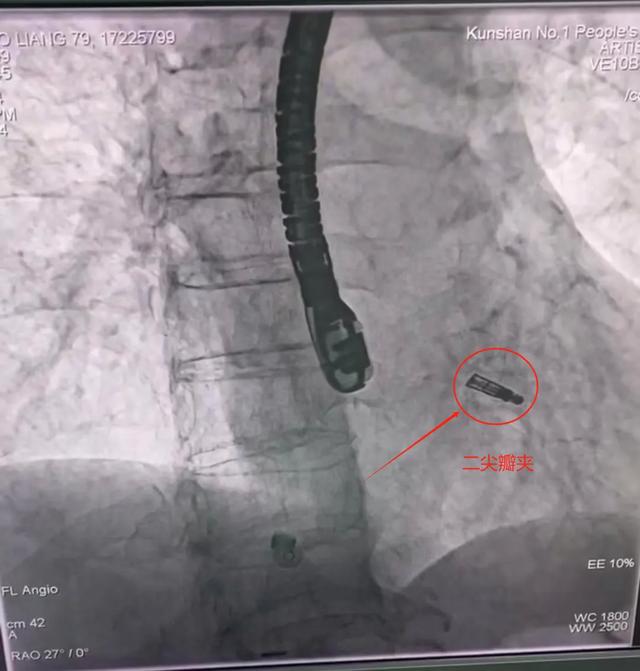

行“經(jīng)導(dǎo)管二尖瓣鉗夾術(shù)”

行經(jīng)導(dǎo)管二尖瓣鉗夾術(shù)